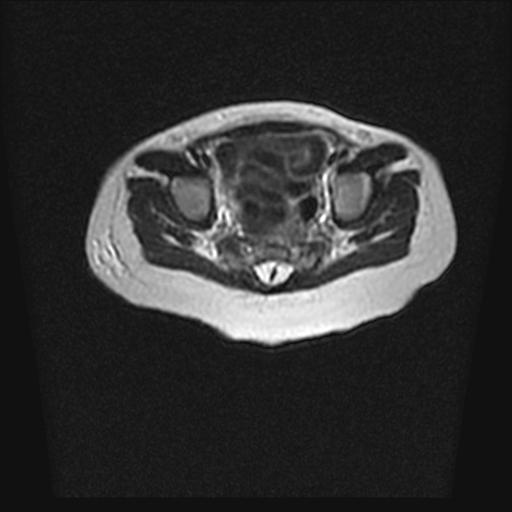

四个月的女婴,ct示脊膜膨出.

脂肪脊髓脊膜膨出

脊柱裂、脊膜膨出